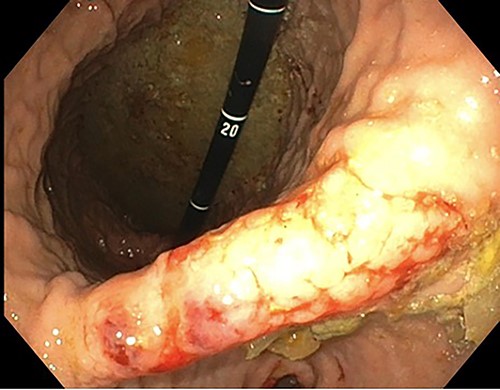

A 76-year-old lady presented to the outpatient clinic with a history of lower abdominal bloating and lethargy for 1 week. The patient denied abdominal pain, nausea, altered bowel habits or GI bleeding. Her past medical history included gastroesophageal reflux disease, ulcerative colitis and a previous hysterectomy. Physical examination exhibited pallor of the conjunctiva, distended abdomen with visible peristalsis on inspection but soft, non-tender on palpation and absence of ascites. Laboratory testing found normocytic normochromic anaemia, thrombocytosis and a positive myeloma screen with elevated kappa to lambda free light chain ratio despite normal renal and liver function. An ultrasound of the abdomen was unremarkable. Computed tomography (CT) with IV contrast of the abdomen revealed diffuse thickening of the small and large bowel with the small bowel dilated throughout. Magnetic resonance imaging of the small bowel showed multiple abnormally thickened loops of the jejunum and proximal ileum with a maximal wall thickness of 0.9 cm (Figs 1 and 2). Gastroscopy revealed severe distal oesophagitis, the stomach contained patchy telangiectasia and gastritis with sloughy mucosa at the incisura in addition to duodenitis with stricture at the second part of duodenum (D2) (Figs 3 and 4). Histopathology from the biopsies of the gastric incisura, D2 and the proximal jejunum displayed reactive changes with intramucosal haemorrhage and extensive deposition of pink amorphous, eosinophilic material on haematoxylin & eosin (H&E) stain. The deposits were predominantly seen in the proximal jejunum with a positive Congo red stain showing apple-green birefringence under polarized light (Figs 5 and 6). The patient was referred to Haematology, and a bone marrow aspirate and trephine biopsy revealed proliferation of 15% mature plasma cells consistent with the diagnosis of myeloma.

Endoscopic retroflexed view of the stomach showing gastritis, patchy telangiectasia and sloughy mucosa at the incisura.